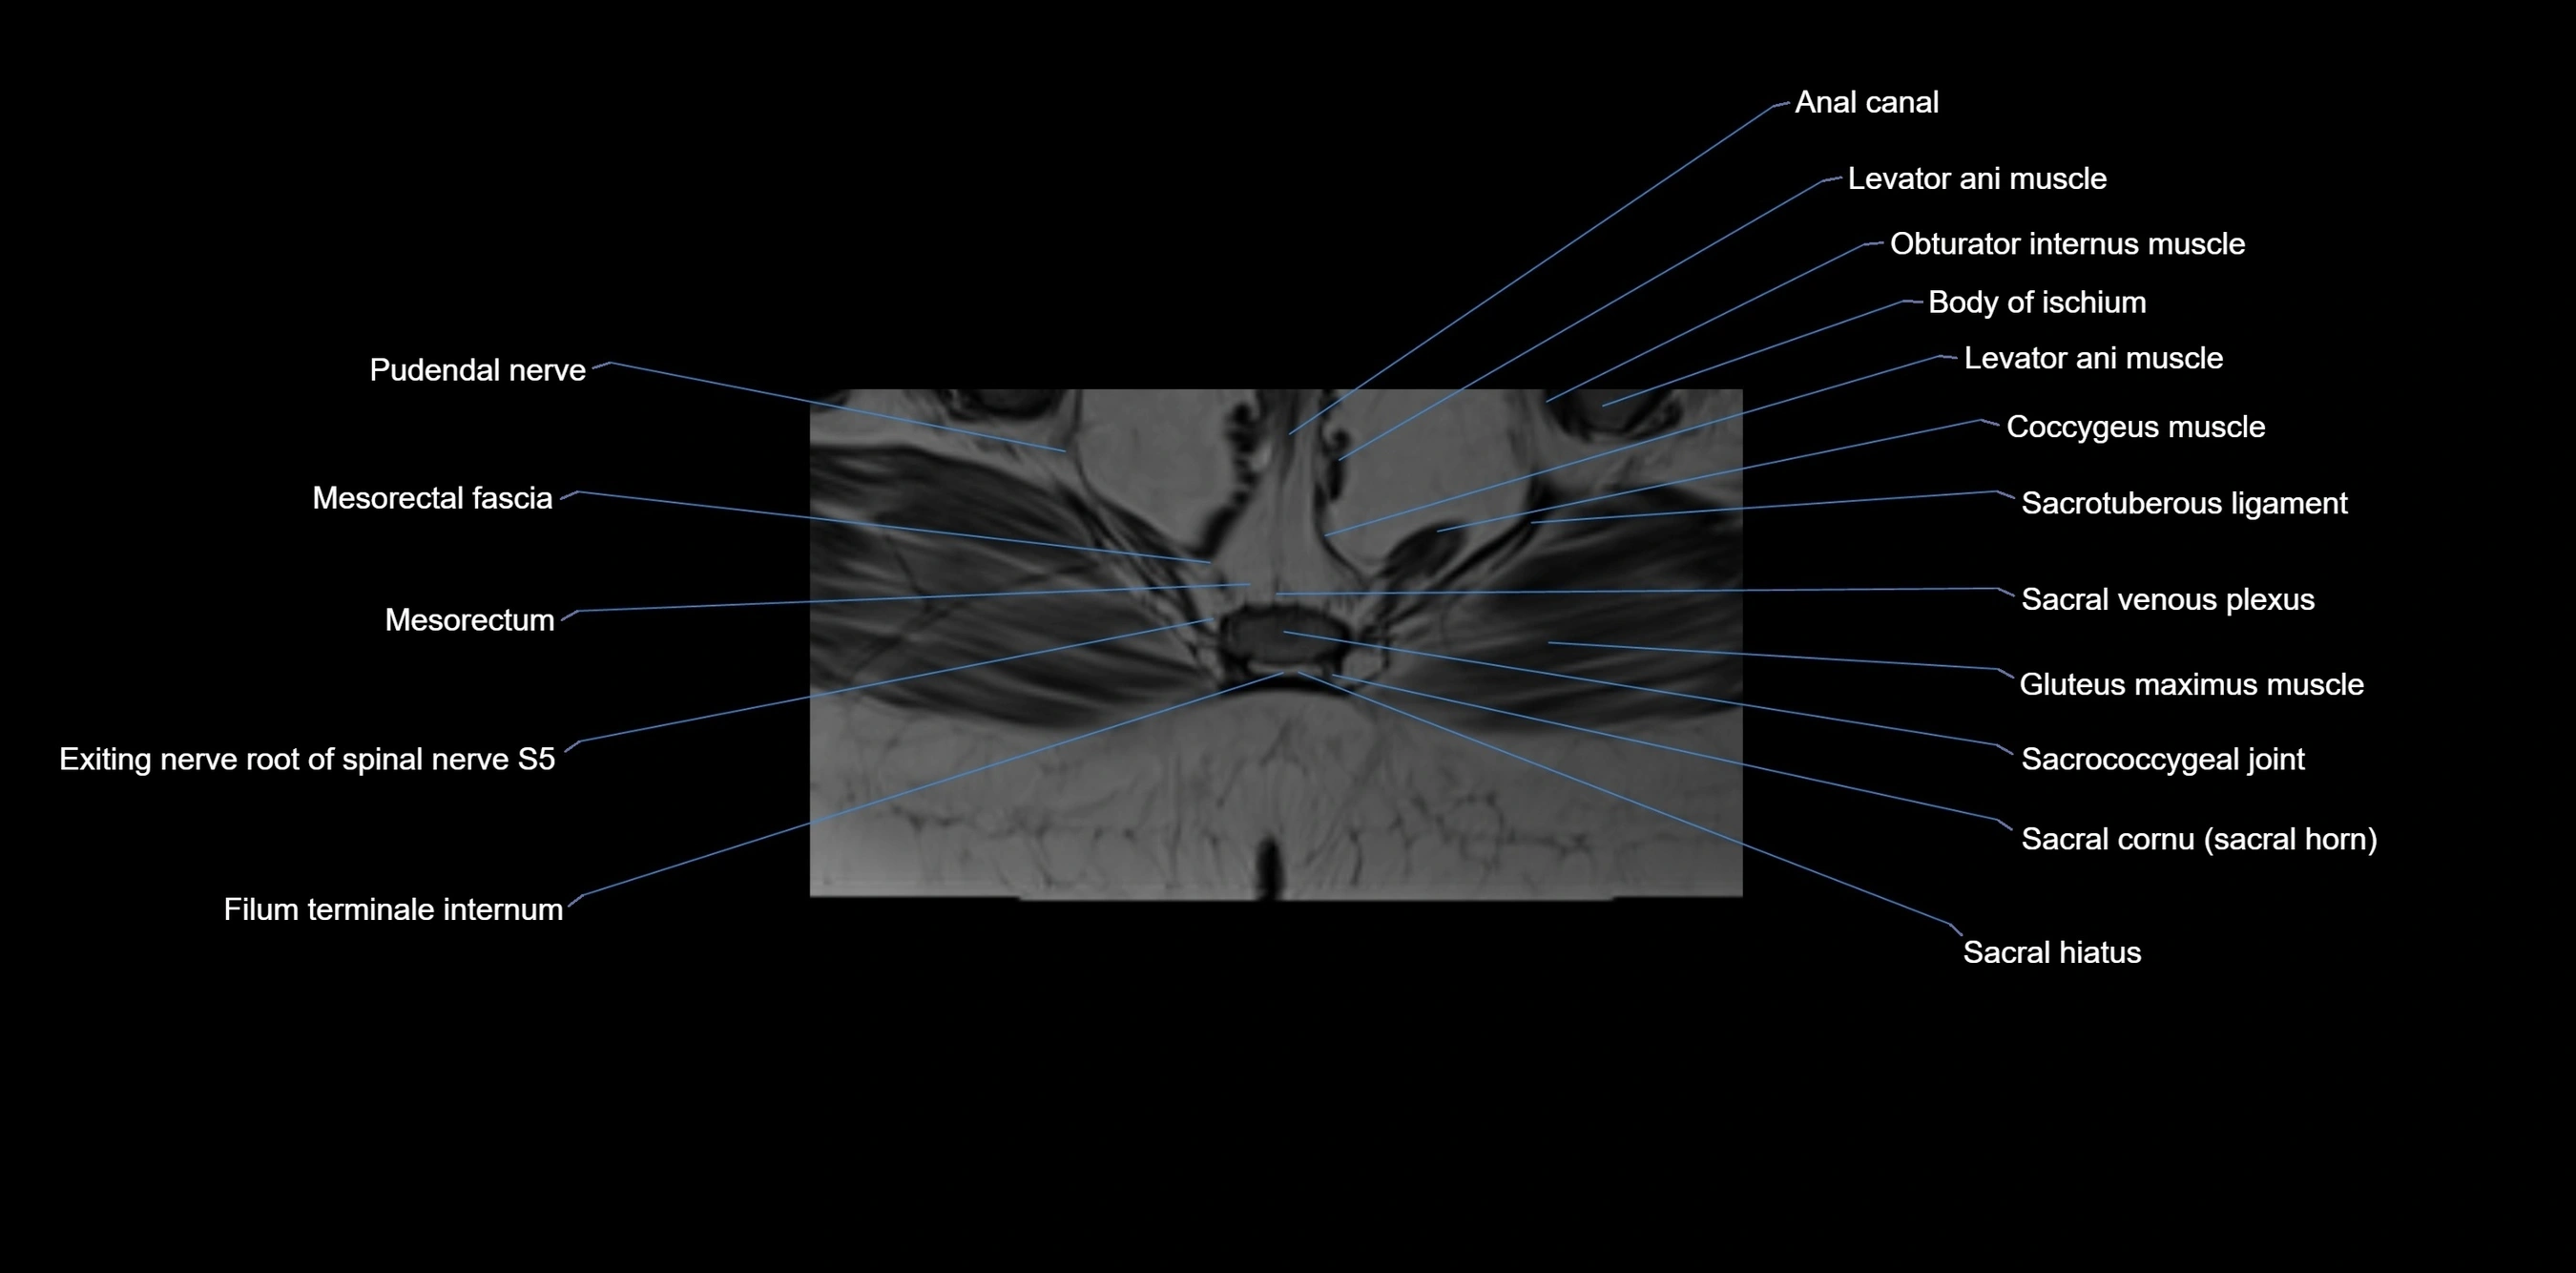

MRI image

image